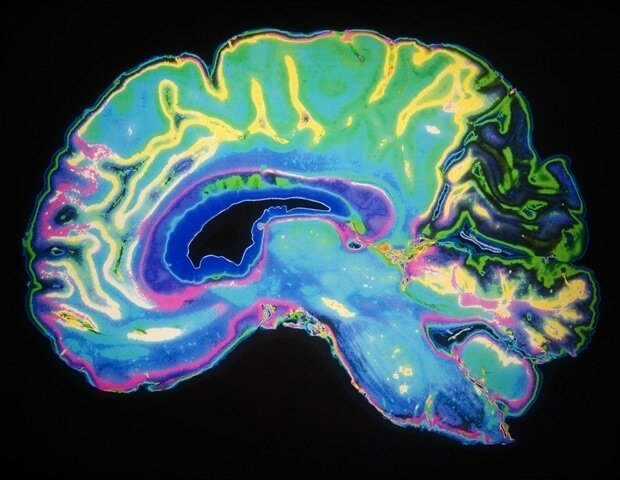

عامل مختل کننده حافظه و یادگیری

عامل مختل کننده حافظه و یادگیریبر اساس تحقیقات دانشگاه لستر انگلستان مشخص شد چه عاملی عملکردهای شناختی مانند حافظه و یادگیری را با افزایش سن دچار اختلال می‌کند.

به گزارش ایسنا و به نقل از نیوز، نتایج این تحقیقات نشان می‌دهد که میزان کلسیم، نقش مهمی در عملکرد سلول‌های خاص در مغز دارد.

پروفسور نیک هارتل از گروه علوم اعصاب­- روانشناسی و رفتار دانشگاه لستر میزان کلسیم موجود در هیپوکامپ، بخشی از مغز که در یادگیری و حافظه درگیر است را مورد بررسی قرار داد.